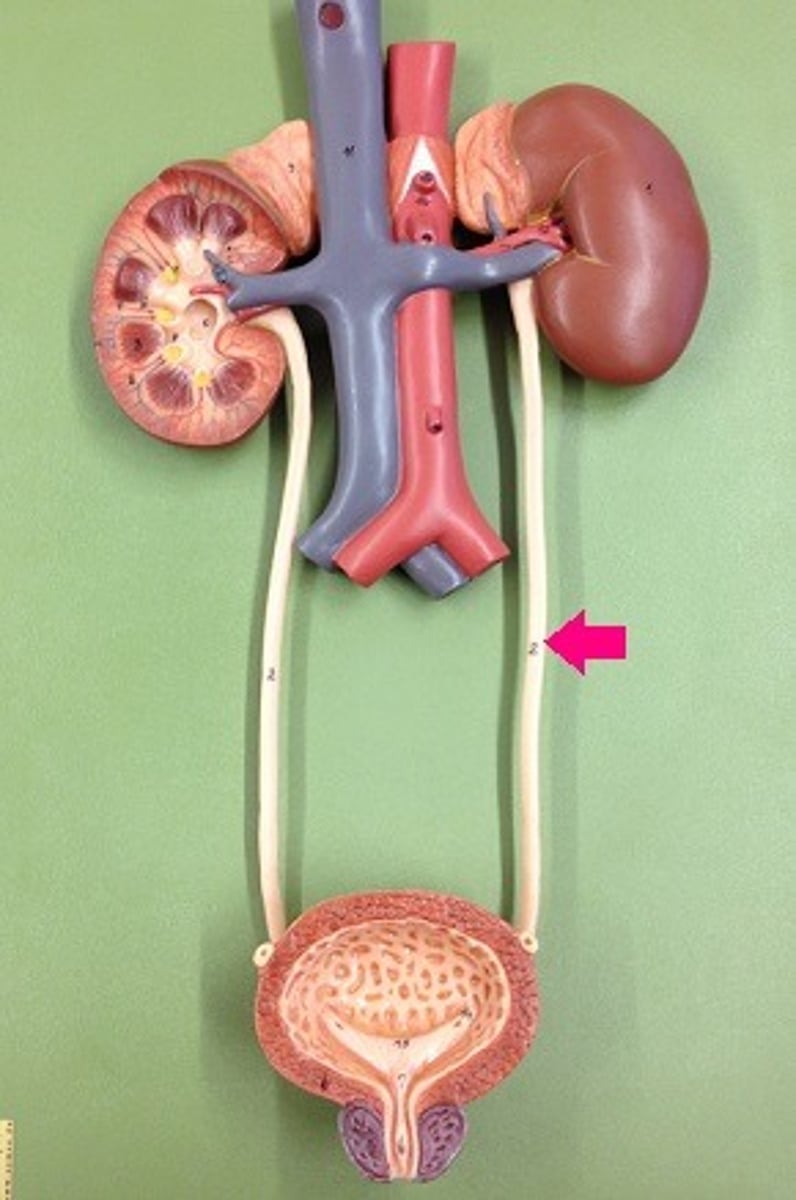

ureter

ureter

Pin in the middle

urinary bladder

urinary bladder